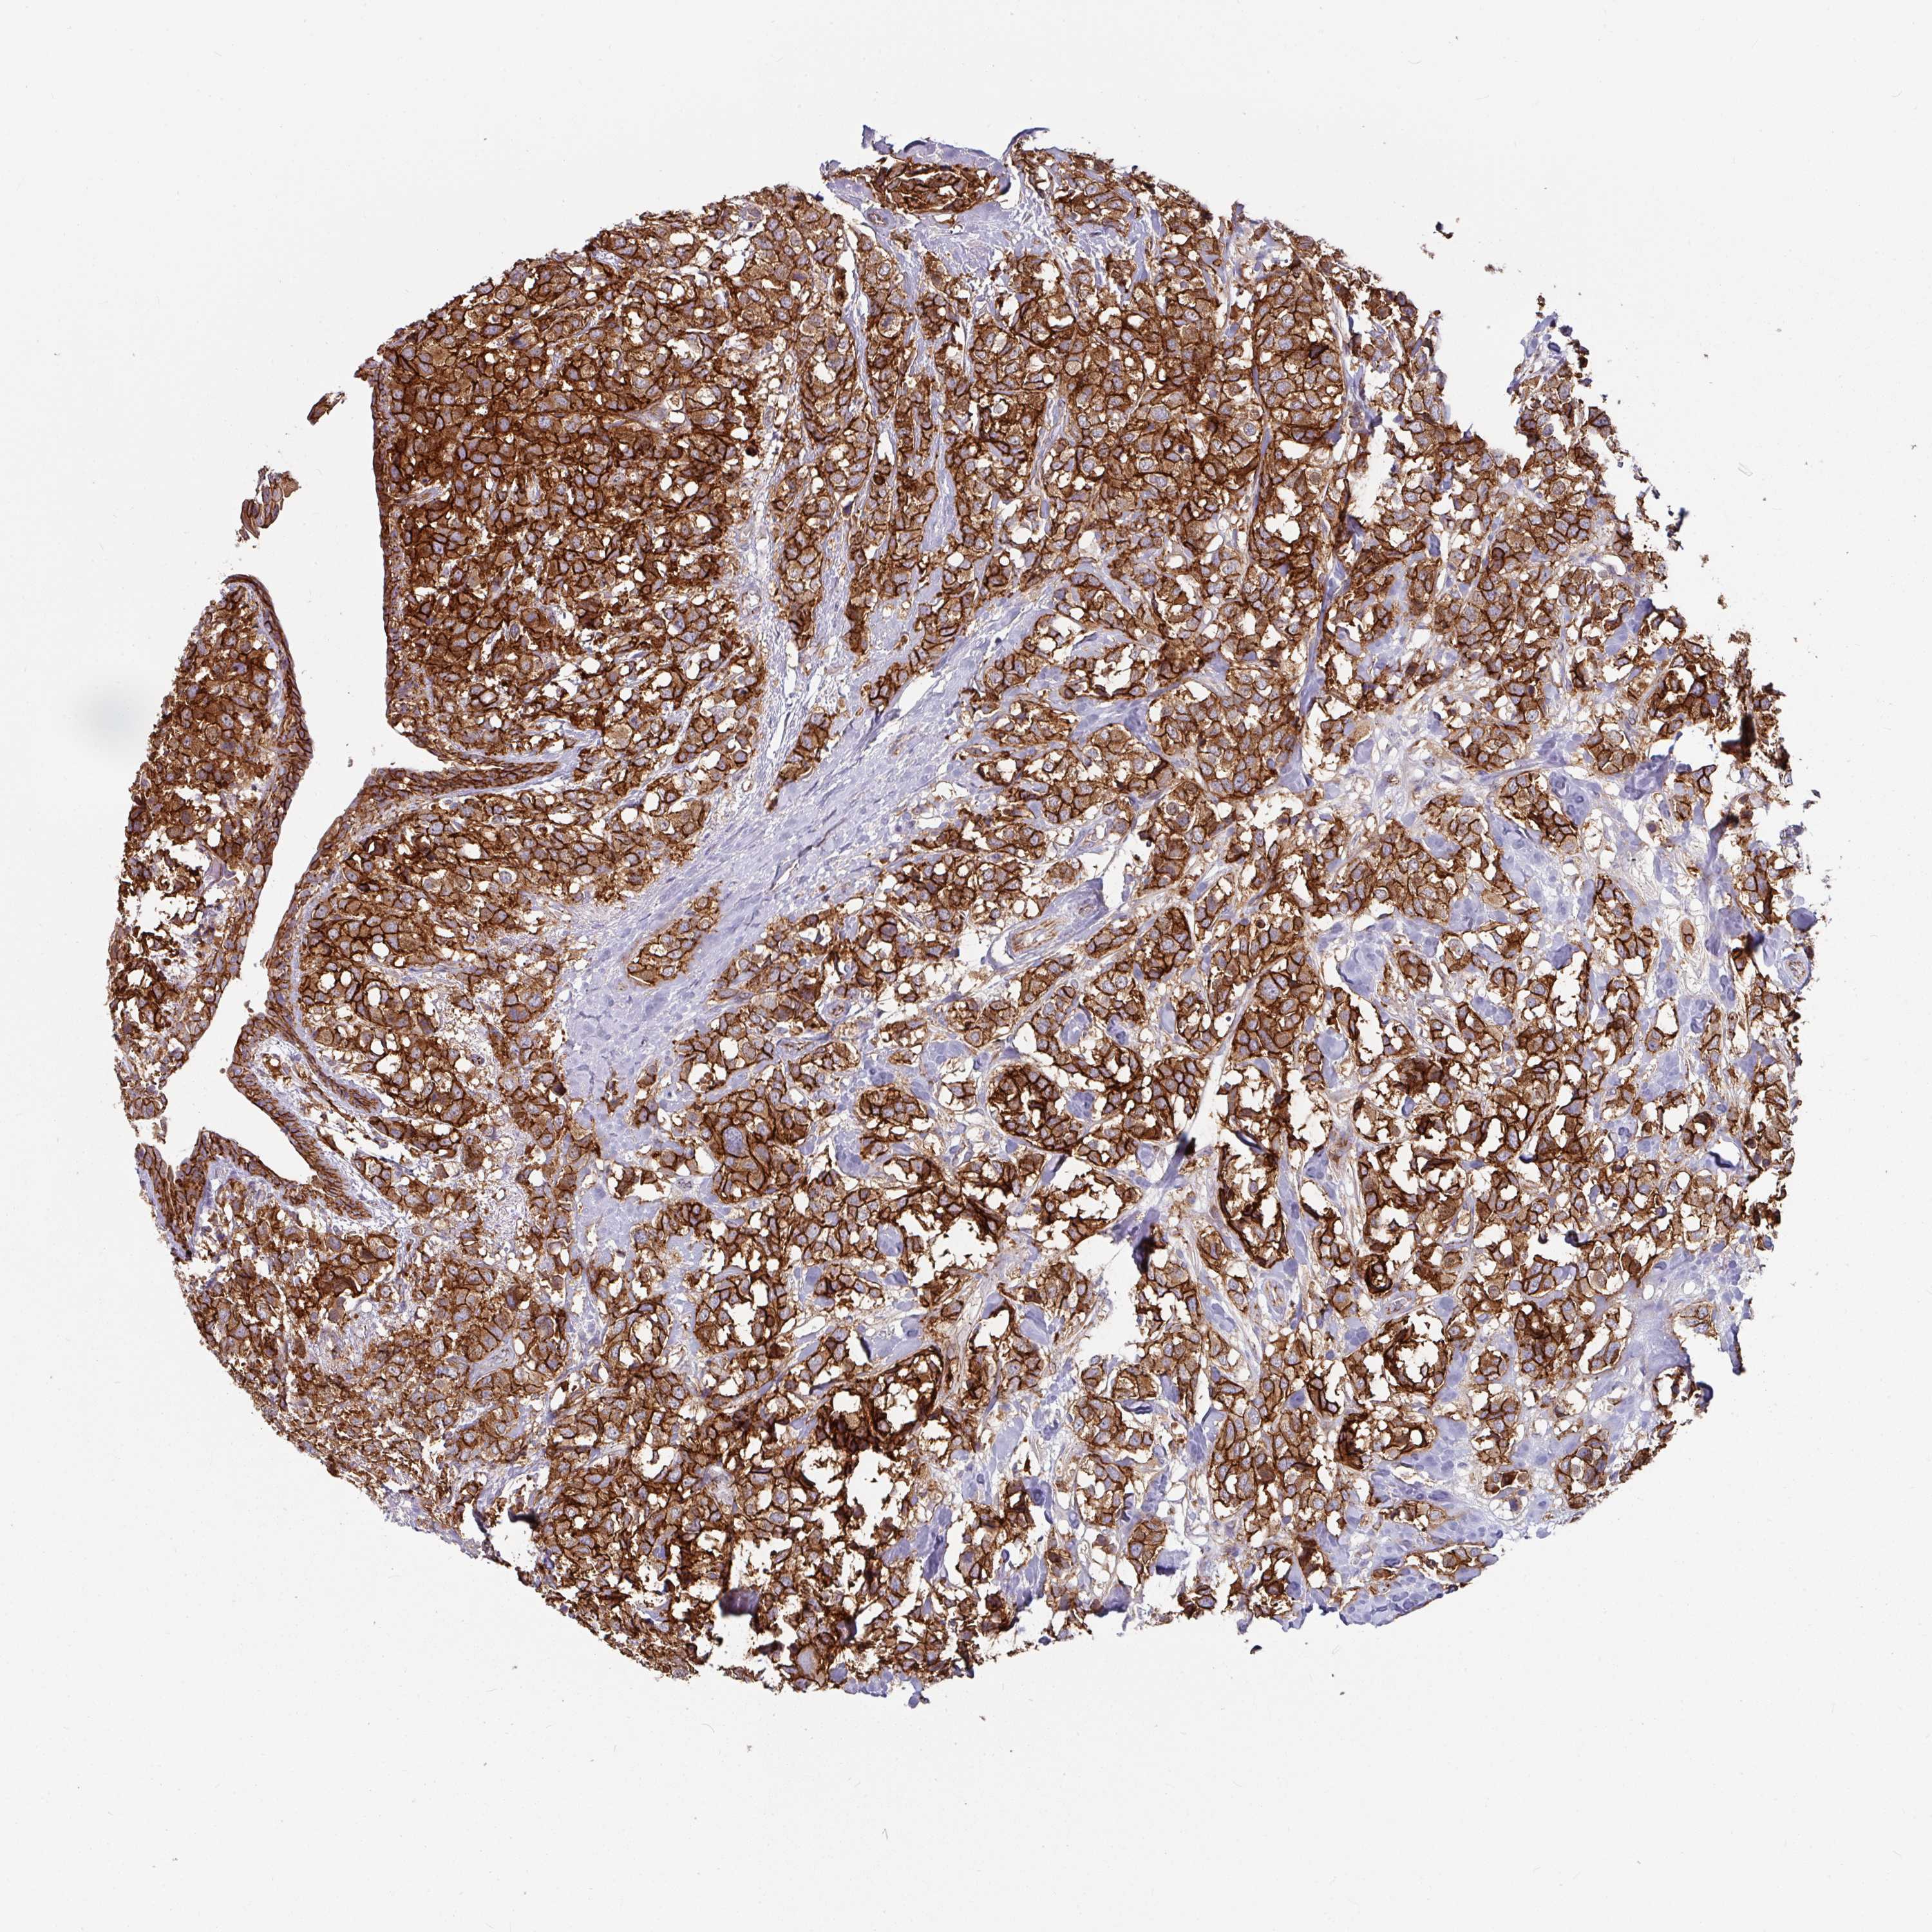

CANCER BREAST CANCER Show tissue menu

BRCA TCGA BRCA VALIDATION PROTEIN EXPRESSION